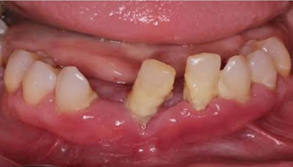

Retained Dental roots

After crown fracture there is only root present in oral cavity, which required extraction.

દાંતના મૂળિયા

જ્યારે દાંતનો ચાવવાનો ઉપયોગી ભાગ સડી ને કે અન્ય કારણોસર તૂટી ગયો ગયો અને ખાલી મૂળિયા રહ્યા હોય.